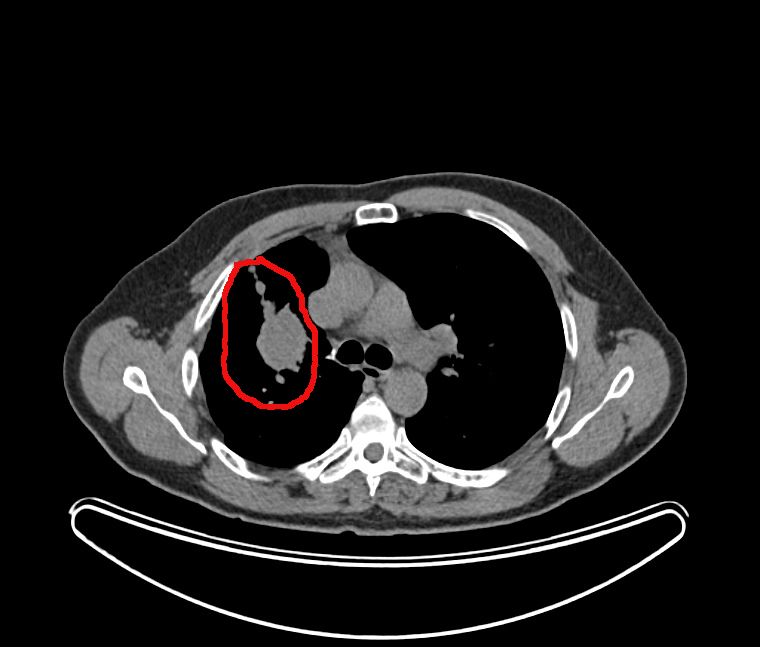

Vue de la tumeur:

il s’agit de cette grosse tache blanche dans le poumon droit (à gauche sur les images)